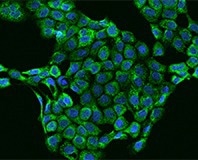

Immunofluorescence staining of Inhibin beta B in A431 cells. Image Credit: Sino Biological Inc.